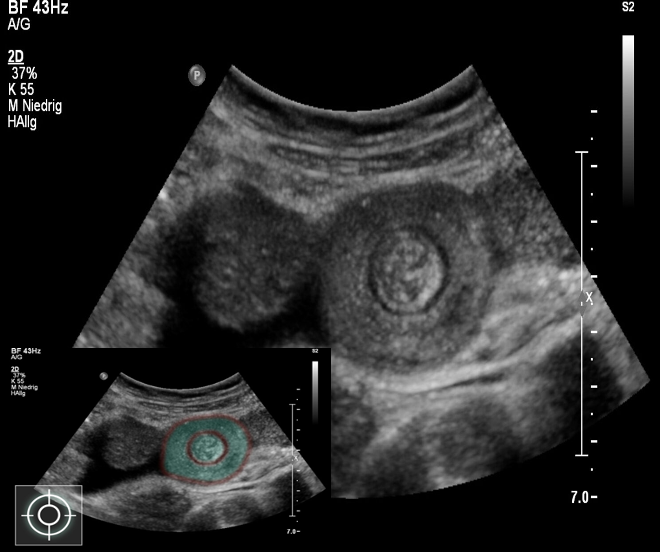

- Ultrasound is the method of choice and diagnostic â target sign.

Target sign

- â Doughnut shape

- â Target sign

- â Pseudkidney sign

Abdominal ultrasound (best initial test): often sufficient to confirm diagnosis Â

- Target sign : The invaginated portion of bowel appears as rings on a target on ultrasound.Â

- Pseudokidney sign: This âpseudokidneyâ is made up of longitudinal layers of bowel wall.

Target sign in intussusception

Ultrasound abdomen (bowel; transverse plane)

Concentric alternating hyperechoic and hypoechoic rings are visible. The hyperechoic rings (green overlay) are formed by mucosa and the hypoechoic rings (red overlay) by submucosa. Together the alternating layers produce a target-like appearance (target sign; bullâs eye sign).